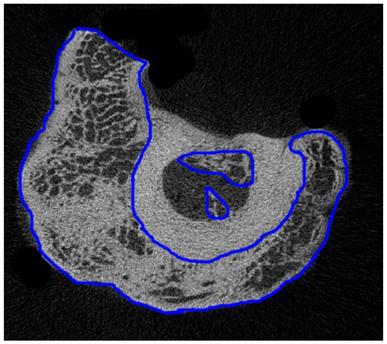

The region of interest (ROI) in the 2D micro-CT image was selected one by one manually. Figure 4 shows a typical ROI on a 2D micro-CT image. Then, the 3D microstructures were built from 2D ROIs and used for calculation of microstructural parameters by CTAn (CTAn, Skyscan, Belgium), and the results are shown in Table 3.

A typical ROI of calluses on a 2D micro-CT image from group W8 (regions of internal and external calluses were drawn by blue lines)